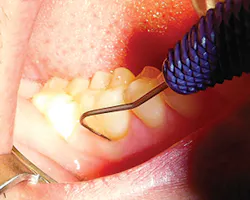

To evaluate for furcation involvement, select a furcation probe (e.g., Nabers or ACE probe). The ACE probe is the next generation of probes, a straight furcation probe that is both flexible and more accurate with a newly designed periodontal probe on the other end that is designed for patient comfort (see Figure 5).

Insert the probe into the furcation locations, as shown on Figure 6. Measure and record any tooth numbers with a furcation grade (I, II, III, or IV). Refer to Glickman guidelines, and see Table 2. Focus on furcations grade I-II for the optimal time and grade III with at least one wall for regenerative treatment, such as guided bone rengeration (GBR) (see Figure 7). If the furcation progresses to a grade IV, the studies now recommend extraction and/or implant placement due to the oral-systemic risk to the patient.6,9